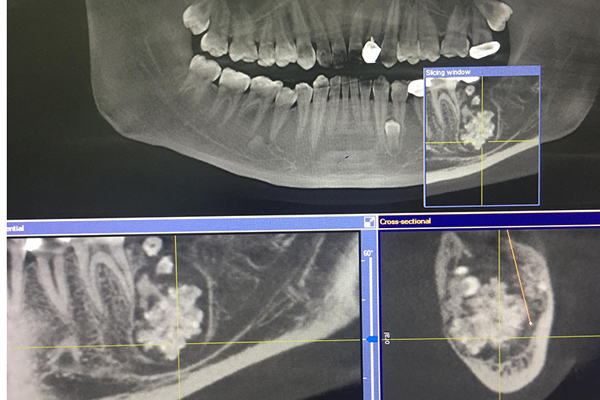

Khi chỉ định chụp X-quang, bác sĩ phát hiện xương hàm dưới có khối u răng kích cỡ 3x4 cm, bên trong chứa nhiều răng to, nhỏ có đầy đủ tổ chức như rằng bình thường, kết lại thành một khối.

Khối u răng của bệnh nhân chứa đầy răng to, nhỏ phía trong